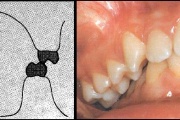

Valehambumus

Hammaste asendianomaaliad on tingitud tavaliselt arenguhäirest.